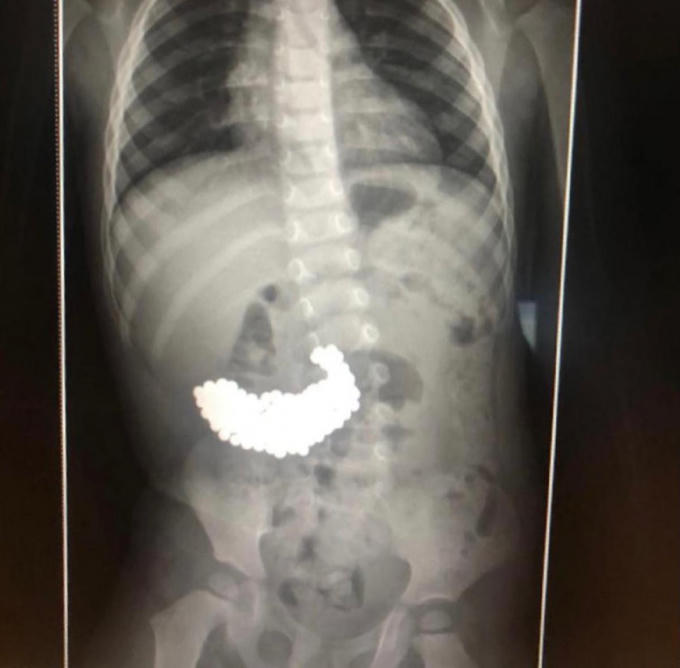

Sau khi chụp X-quang, các bác sĩ vô cùng sốc phát hiện nhiều vật thể kim loại bên trong dạ dày của cậu bé, theo cậu bé này cho biết những viên bi này vào bụng từ 2 tháng trước đó từ một loại đồ chơi cậu từng chơi.

Ảnh chụp X-quang cho thấy nhiều viên bi nam châm trong dạ dày của bé trai. Ảnh: News.com.au